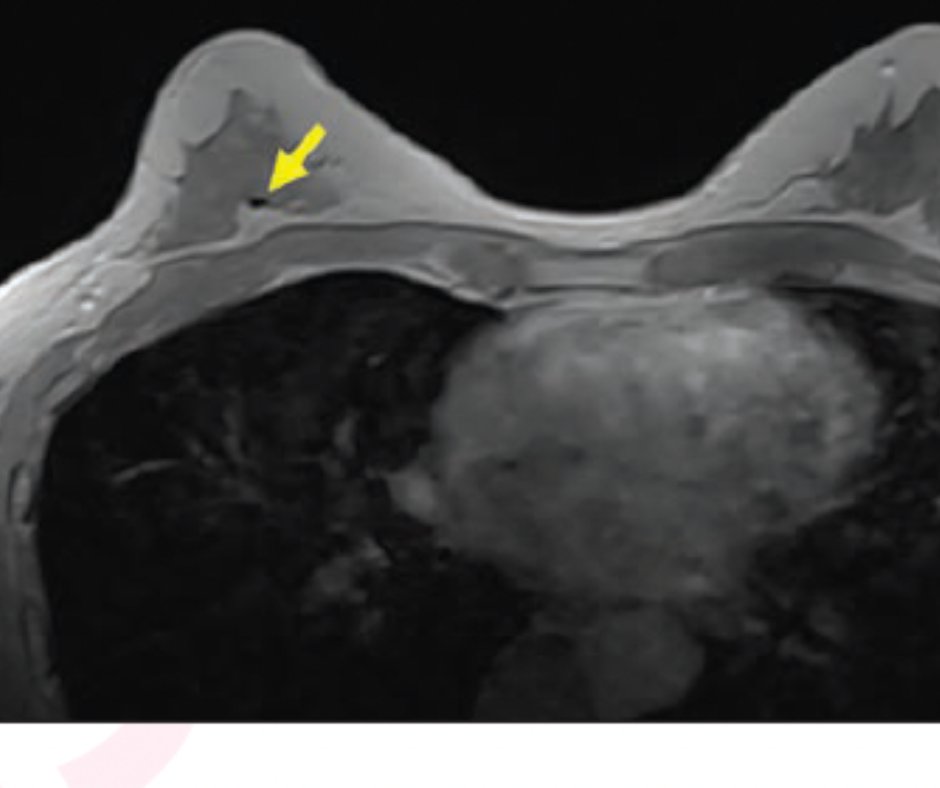

Placement of Marker Clips in breast before neoadjuvant chemotherapy What Are Clips In Breast Biopsy If you’ve had a surgical biopsy on your breast (or you’re about to get one), you may know that your doctor uses a tiny titanium clip. This allows doctors to know the exact location of a previous biopsy, in case more. A very small clip (like a tiny staple usually made of stainless steel or titanium) is left behind in. What Are Clips In Breast Biopsy.

MRI Breast Biopsy Section B Basic Biopsy Technique for Radiologists What Are Clips In Breast Biopsy During a core needle biopsy, a clip may be placed inside the breast (you can’t feel it) to mark the location of the lump. Typically, a tiny tissue marker (also called a clip) is put into the area where the biopsy is done. A very small clip (like a tiny staple usually made of stainless steel or titanium) is left. What Are Clips In Breast Biopsy.